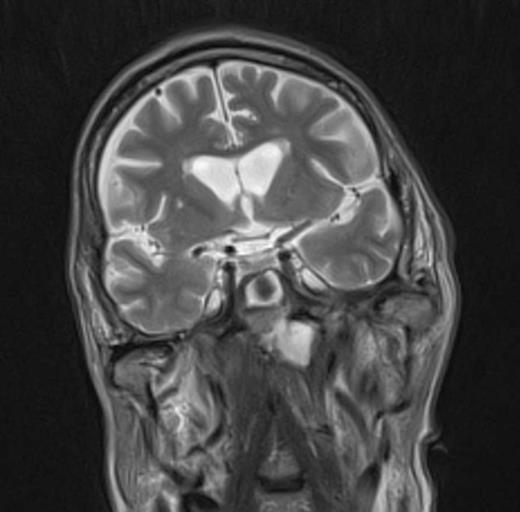

At the tertiary hospital the patient was found to be clinically wasted and weak. He also had rightward uvular deviation, absent gag reflex, weakness of the left sternocleidomastoid and trapezius, House Brackman grade 2 left facial nerve weakness and an immobile left vocal cord. This was the first time a cranial nerve examination was recorded. MRI and SPECT/CT with Gallium tracer was performed, the images acquired from which illustrate the severe extent of disease (figures 1 to 5).

He was diagnosed with MOE with extensive skull base osteomyelitis producing multiple lower cranial neuropathies. Biopsy performed by ORL/ENT surgeons grew Scedosporium apiospermum and given the extent of the infection a palliative approach was agreed upon with the patient and family.